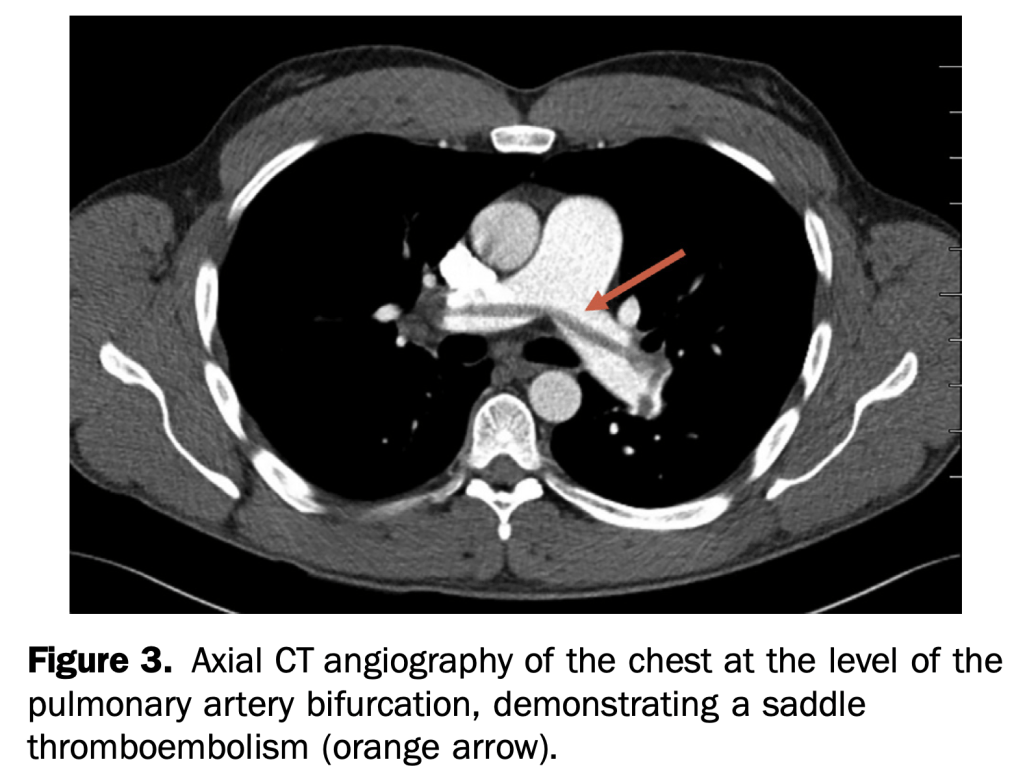

- An otherwise healthy 35-year-old active duty military infantryman presented to the emergency department, complaining of intermittent dyspnea over one-week duration, which was worsened by exertion. He recalled some unusual left leg cramping three weeks before and reported an uncomplicated tooth extraction one week before, but denied any invasive surgeries.

- This case demonstrates multiple rare but specific radiographic findings of pulmonary embolism. These include the Westermark, knuckle, and Fleischner signs, in addition to Hampton’s hump.